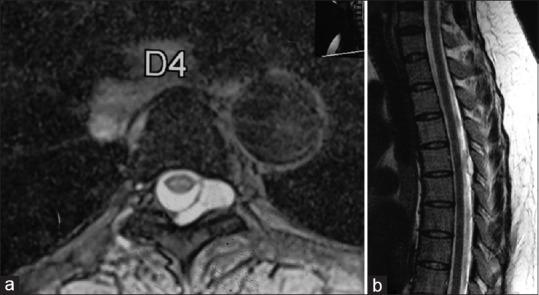

Spinal arachnoid cyst is an uncommon entity, presenting with radiculopathy or paraparesis. These cysts are usually found in intradural extramedullary region; and the extradural region is a rare location. The exact pathogenesis in the existence of these cysts in the extradural region is still debated. In this article, we have retrospectively analyzed the clinical profile of the rare extradural arachnoid cyst (EDAC).

Symptomatic EDACs account <2% of all spinal tumors. The EDACs have communication with the intradural compartment. In our article, we have discussed the approach and management of EDAC, including minimally invasive percutaneous procedures.

脊髓蛛网膜囊肿是一种罕见的疾病,表现为神经根病或轻截瘫。这些囊肿通常位于硬脊膜内髓外区域;而硬脊膜外区域则是罕见的发病部位。硬脊膜外区域存在这些囊肿的确切发病机制仍存在争议。在本文中,我们回顾性分析了罕见的硬脊膜外蛛网膜囊肿(EDAC)的临床特征。

有症状的EDAC占所有脊柱肿瘤的比例<2%。EDAC与硬脊膜内腔相通。在我们的文章中,我们讨论了EDAC的治疗方法,包括微创经皮手术。